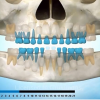

Ülemiste tsentraalsete lõikehammaste (intsisiivide) vahetumine. Retineerunud intsisiivid. Ülemised tsentraalsed esihambad lõikuvad orienteeruvalt 7-8-aastaselt. Enamasti lõikuvad samanimelised jäävhambad paaridena. Normaalne lõikumise järjekord 7, 5-aastselt: vt pilti